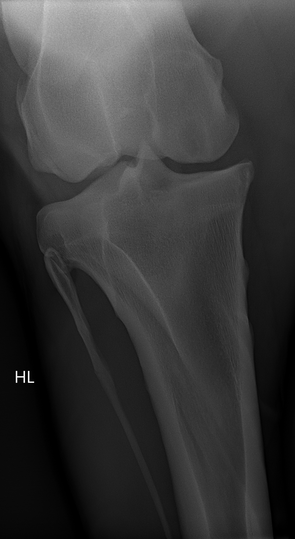

• Röntgenuntersuchung (nach aktuellem Röntgenleitfaden 2018 der Bundestierärztekammer / GPM)

• 6 × Tarsus-Aufnahmen (Sprunggelenk, 3 Ebenen beidseits)

• 4 × Kniegelenk (2 Ebenen beidseits)